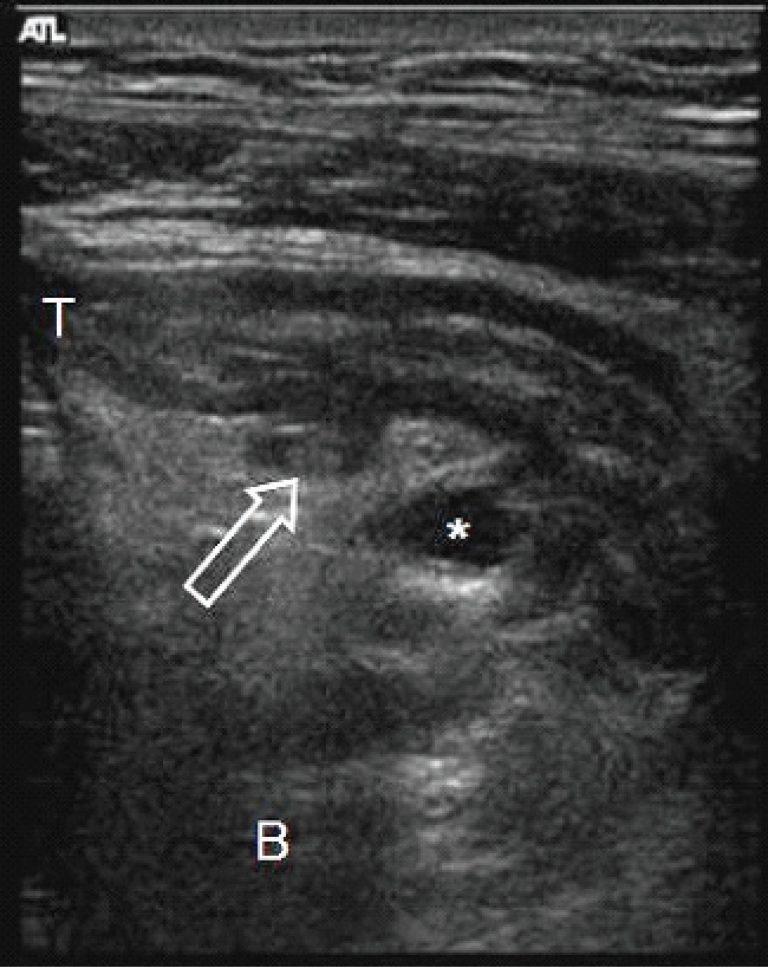

Diverticulite perfurada do apêndice cecal: diagnóstico ultrassonográfico

A diverticulite do apêndice é uma patologia incomum, eventualmente confundida com a apendicite cecal, tendo, porém, maior risco de perfuração e de outras complicações. Seu diagnóstico pré-cirúrgico é raramente realizado, mas pode ser obtido pela ultrassonografia com a demonstração de um divertículo associado a sinais clássicos de apendicite. Relatamos o caso de um homem adulto em que foi possível o diagnóstico ultrassonográfico de diverticulite do apêndice cecal e revisamos os principais aspectos relacionados a essa condição.